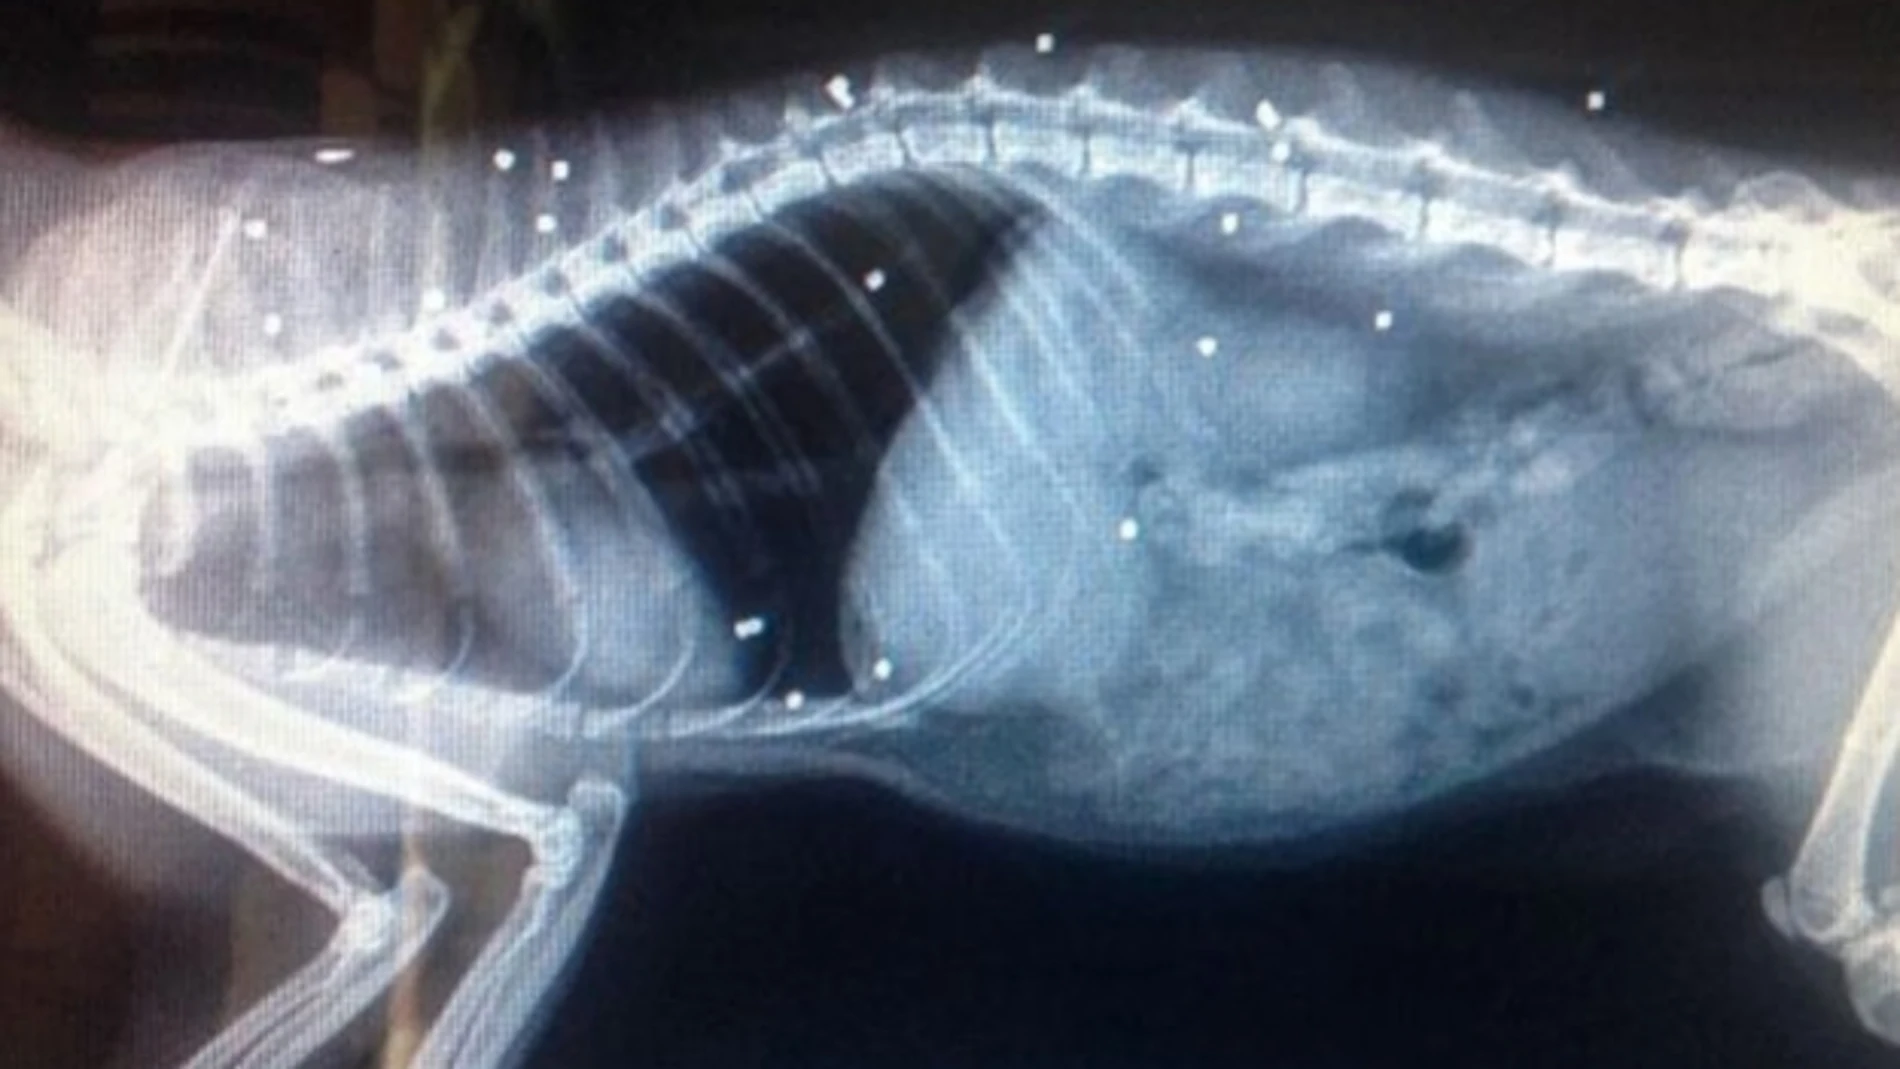

Fue llevado a un veterinario donde fue examinado con rayos X. La radiografía reveló que su cuerpo estaba repleto de perdigones.

Según informa el diario británico Independent, el inspector Adam Jones ha asegurado que tendrán que extirparle el ojo al gato debido a que "una bala impactó en el centro de su ojo causando un desprendimiento de retina". Ha añadido que "le es complicado caminar debido a otra bala en una de sus patas.

Por su parte, el veterinario ha señadado que otras dos balas impactaron en su médula espinal dañándola de forma seria, y que por tanto, "es un milagro que haya sobrevivido".